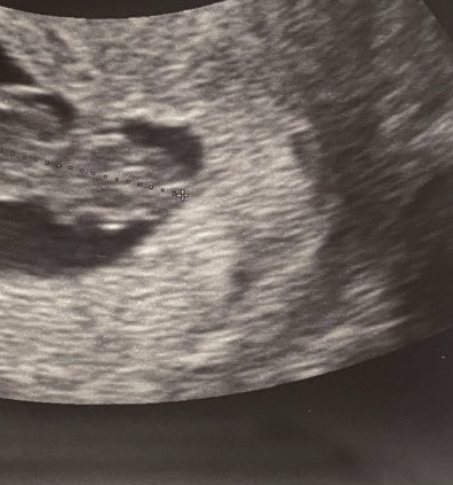

์์ ์ด๊ธฐ์ ํ์์ ๊ฑด๊ฐ ์ํ๋ฅผ ํ์ธํ๋ NIPT(๋น์นจ์ต์ ์ฐ์ ๊ฒ์ฌ)๋ ์ผ๋ฐ์ ์ผ๋ก ์์ 10์ฃผ ์ดํ๋ถํฐ ๊ฐ๋ฅํฉ๋๋ค. ์ด๋ ์ด ์๊ธฐ๊ฐ ๋์ด์ผ ํ์ DNA๊ฐ ์ฐ๋ชจ ํ์ก์ ์ถฉ๋ถํ ์กด์ฌํ๊ธฐ ๋๋ฌธ์ ๋๋ค.

NIPT ๊ฒ์ฌ๋ ํนํ ๊ณ ์ํ๊ตฐ ์์ฐ๋ถ(35์ธ ์ด์, ์ผ์์ฒด ์ด์ ํ์ ์์ ๊ฒฝ๋ ฅ์, ์ด์ํ ์ด์ ์๊ฒฌ์ ๋ฑ)์๊ฒ ์์ 10-12์ฃผ ์ฌ์ด์ ๊ถ์ฅ๋ฉ๋๋ค. ์กฐ๊ธฐ ๊ฒ์ฌ๋ฅผ ํตํด ์์ ๊ด๋ฆฌ ๊ณํ์ ๋น ๋ฅด๊ฒ ์๋ฆฝํ ์ ์๋ค๋ ์ฅ์ ์ด ์์ต๋๋ค.